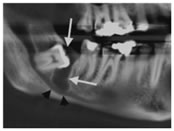

1. Radicular (periapical or apical periodontal) cyst: It is the commonest odontogenic cyst. It occurs secondary to a periapical inflammatory lesion of a non-vital tooth root or a residual cyst, which occurs after loss or removal of the tooth (Fig. 1). It is characterized by its location near the apex of a carious or heavily restored non-vital tooth, mostly a maxillary incisor or canine. It is similar to a periapical granuloma, but its size is generally larger (more 20 mm), with a rounder outline, and a well-defined border. It appears as a well-circumscribed corticated radiolucent lesion at the apex of the nonvital tooth. Cortical expansion may be detected with large cysts (Fig. 2). it may cause resorption of root of the affected tooth displace nearby structures as the neighbouring teeth or the mandibular canal. in MRI, periapical cyst present high T2 (due to high fluid content) and variable T1 signal intensity (Fig. 3). Contrast-enhanced MR show an enhancing cystic wall which is consistent with inflammatory process.9

Figure1: Radicular cyst. Cropped panoramic tomogram shows a well-defined cyst (arrows) related to the upper right central incisor. The root canal of this tooth is widened (arrowhead).

4

Figure 4: Dentigerous cyst (white arrows) related to an unerupted right mandibular third molar, shown on a panoramic MIP reconstruction from a CT of the mandible. Note the mild inferior displacement of the inferior alveolar canal (black arrowheads) by the cyst.